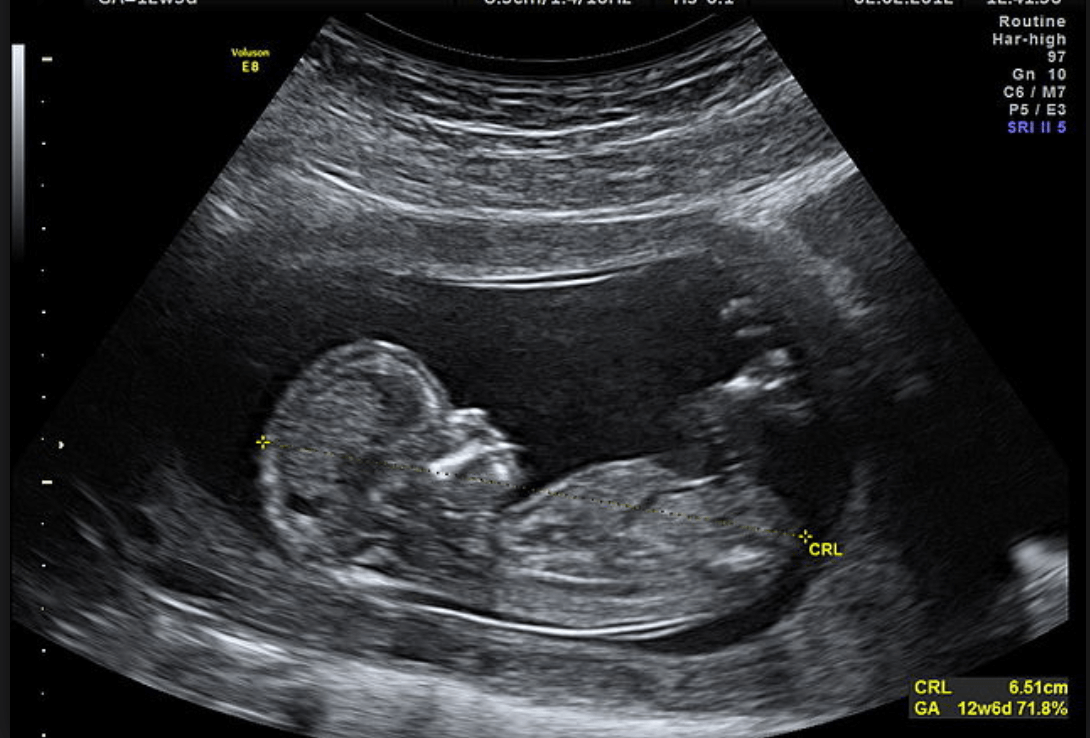

Denne ultralyden utføres for å observere om svangerskapet er levedyktig. Den observerer om det er et levende embryo, om det er en fostersekk og antall embryoer til stede. Også størrelsen på fosteret måles, fra hodeskallen til halebenet, for å bestemme tidspunktet for svangerskapet.